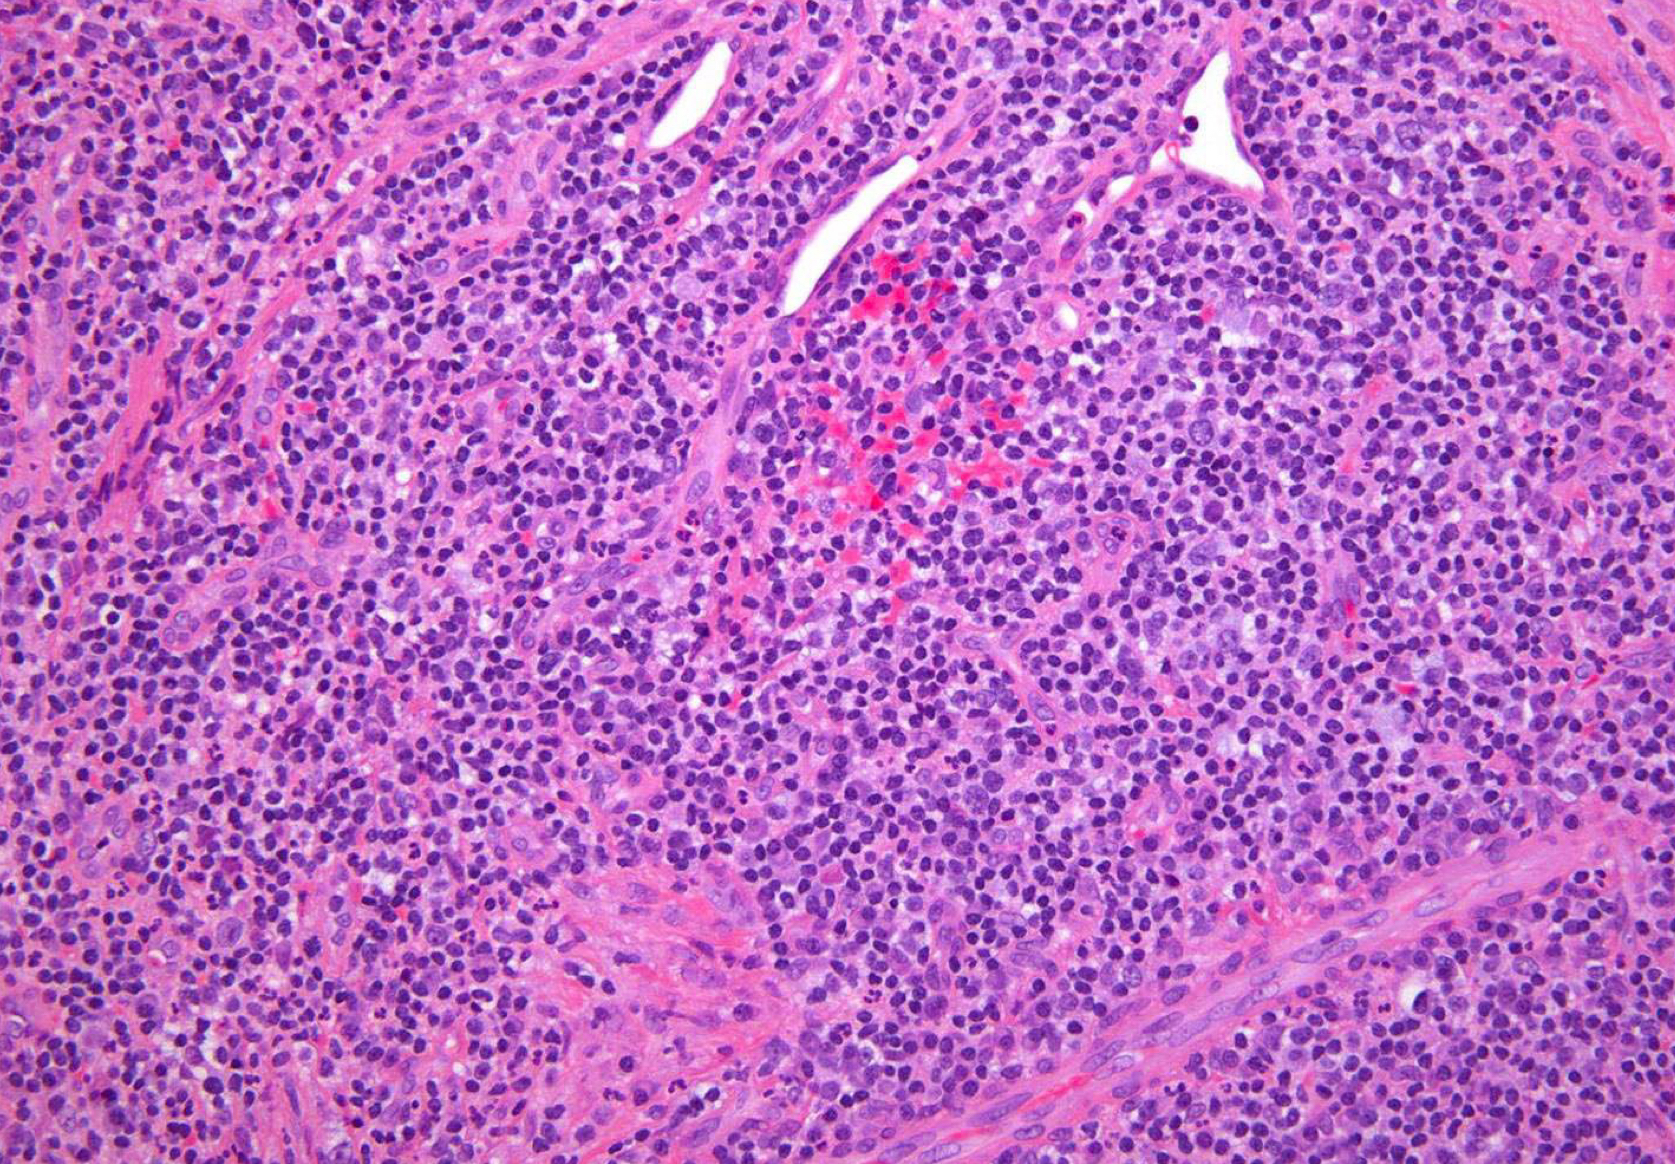

periapical granuloma; granulation tissue w neutrophils, lymphocytes, plasma cells, vascular channelsÂ

which potential result of periapical inflammation?

periapical granuloma; fibroblasts

periapical granuloma; lymphocytes